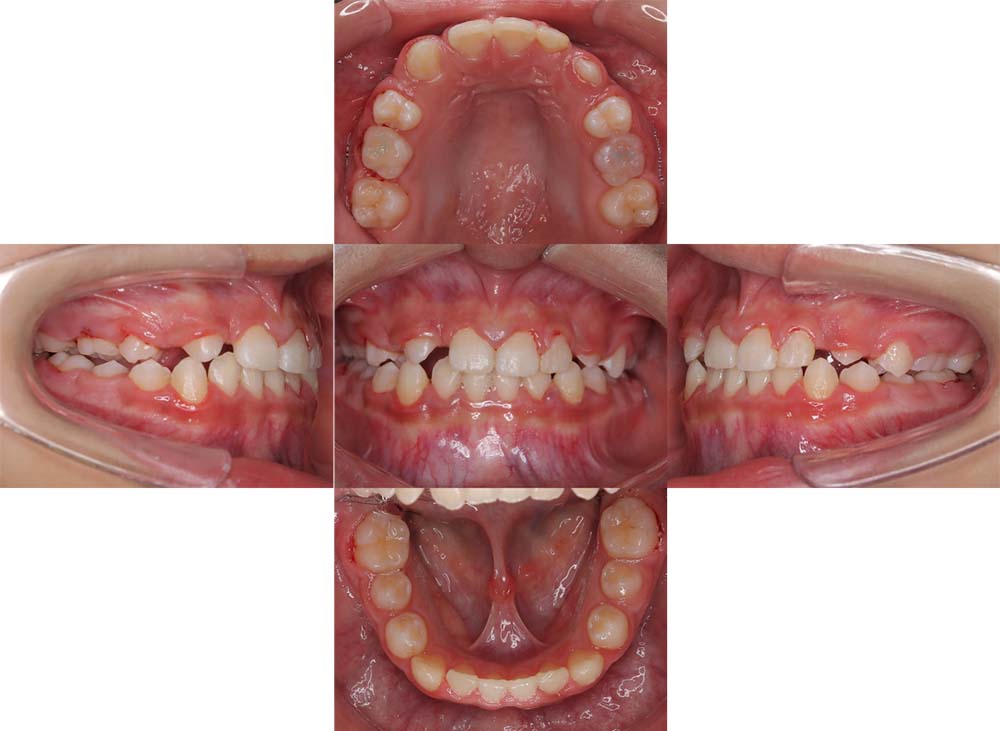

症例10

| 主訴 | 前歯が反対に噛んでいる |

| 診断名あるいは主な症状 | 反対咬合 |

| 年齢/性別 | 9歳・男児 |

| 矯正ステージ | 子どもの矯正治療 |

| 治療方法 | リンガルアーチ |

| 抜歯部位/抜歯有無 | – |

| 治療内容 | リンガルアーチにて反対咬合を改善。その後は成長と生え変わりの定期的なチェックを行った。 |

| 費用 | 30万円程度(2025.5での料金となります。) |

| 治療期間 | 1年0ヶ月程度 |

| 主なリスク・副作用 | 痛み、歯根吸収、歯肉退縮、虫歯、後戻り |